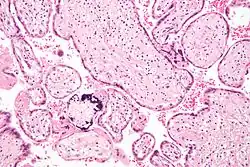

| Micrograph of cytomegalovirus (CMV) infection of the placenta (CMV placentitis), a vertically transmitted infection: The characteristic large nucleus of a CMV-infected cell is seen off-centre at the bottom right of the image, H&E stain. | |

Apart from infecting the fetus, transplacental pathogens may cause placentitis (inflammation of the placenta) and/or chorioamnionitis (inflammation of the fetal membranes).